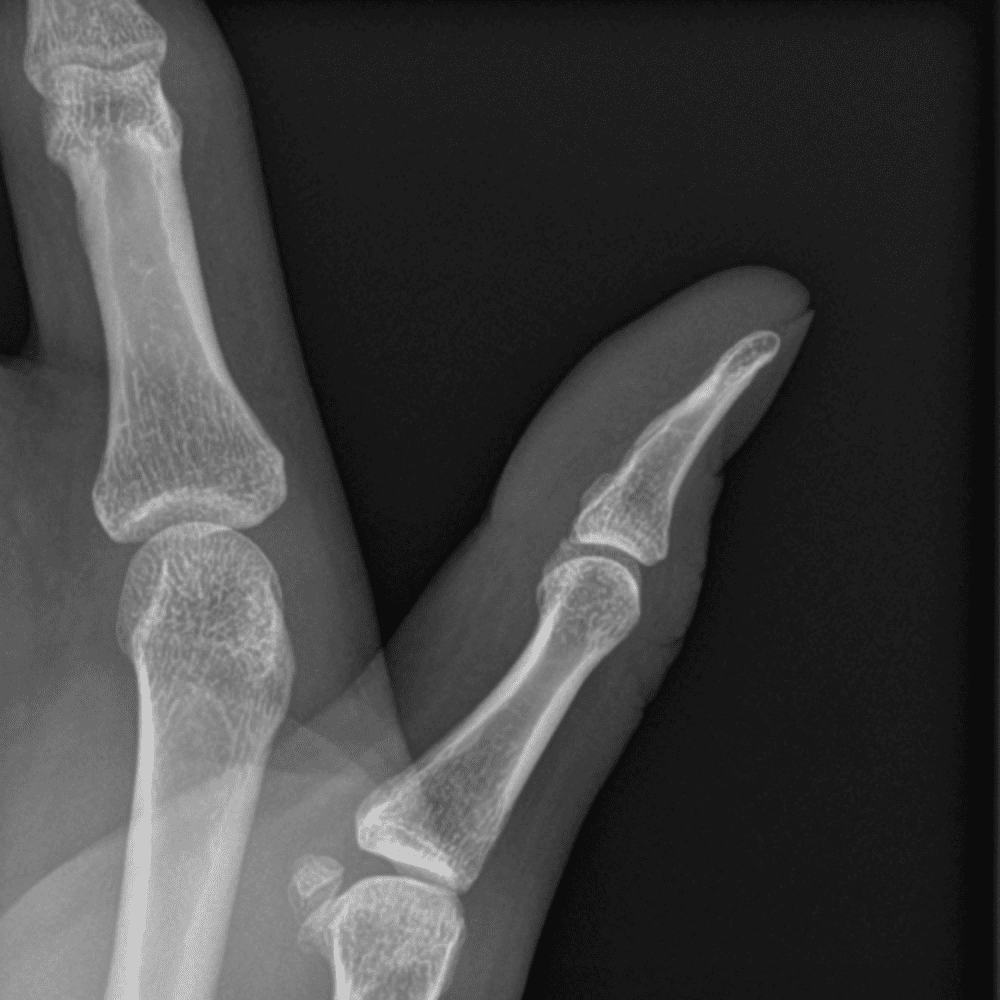

Simuliert den Dienst durch subtile oder schwierige Fälle und einige Normalbefunde.

30 Fälle